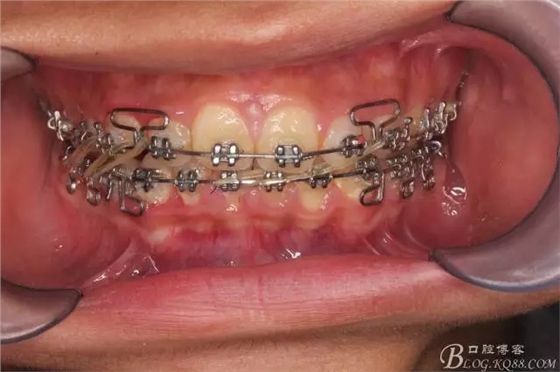

看看口內照吧!真象“大暴牙”v假象“大暴牙”

三度深覆合,三度深覆蓋,尖牙,磨牙均二類關系!

佩戴三個月的FR2, 效果奇佳!前牙基本達到淺覆蓋,淺覆合!接下來進入二期直絲弓固定正畸,排齊階段!

接下來盡管配合些雙側后牙對角牽引,咬合關系依,不盡人意。

下頜配合多曲方絲,三角牽引,調整咬合。

中線不齊,咋辦?繼續(xù)哄哄患者配合,2牽+斜牽。

努力沒有白費,中線基本對齊!

尖牙關系中性,磨牙關系中性,咬合鎖結良好!